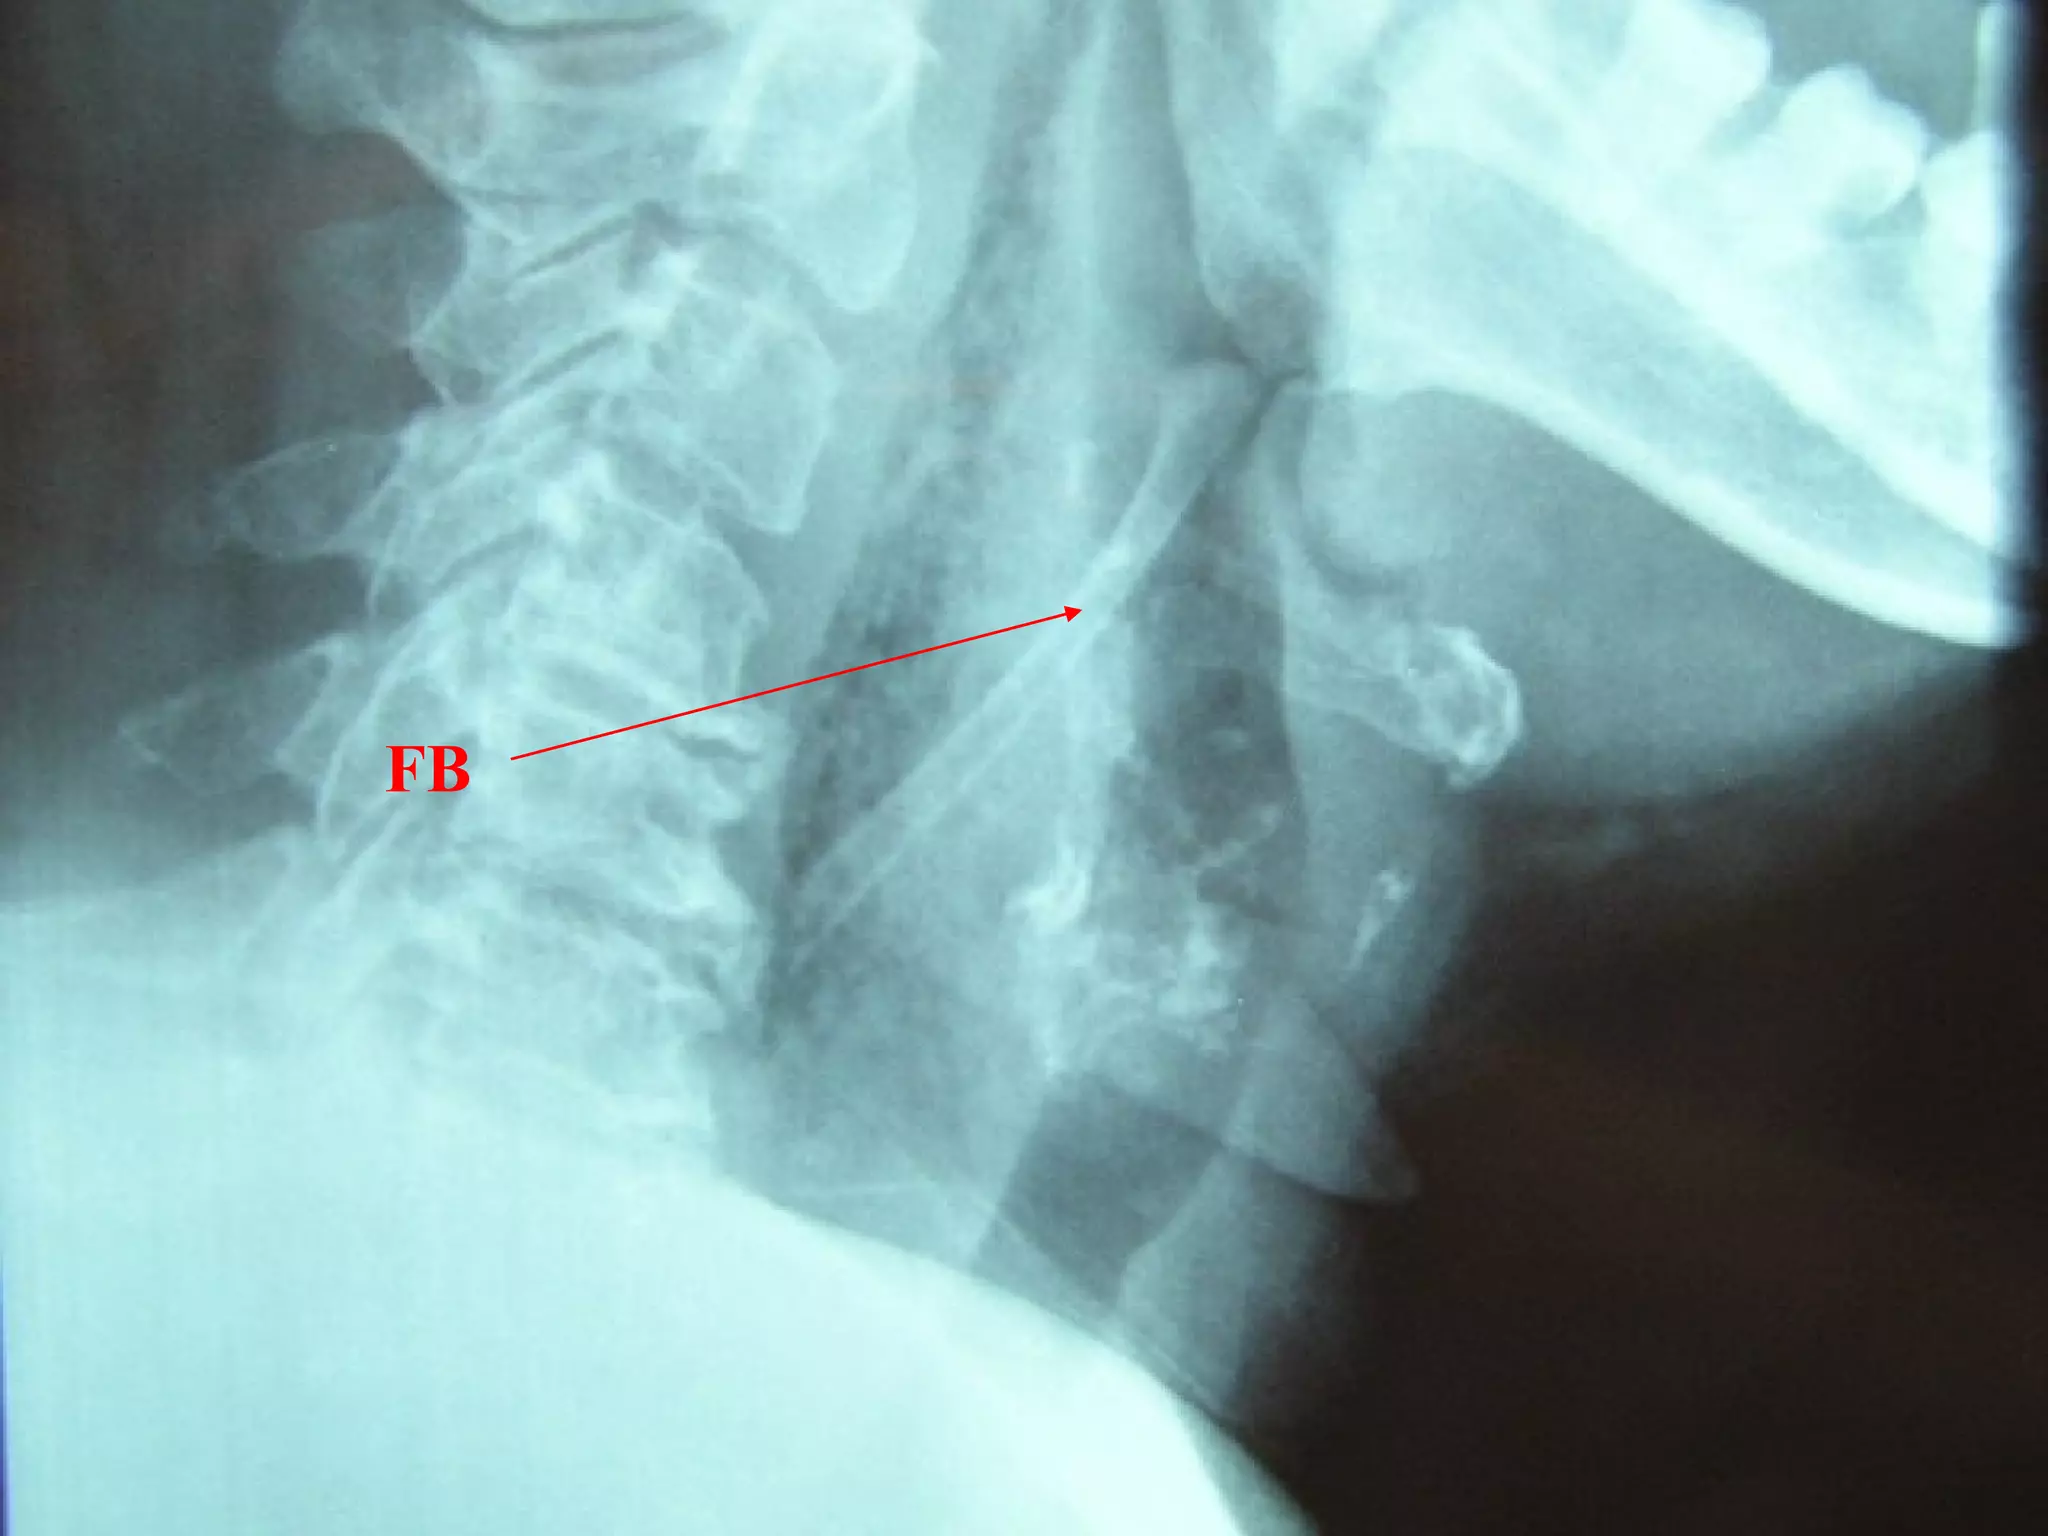

FB Throat - Investigations

Lateral neck XR

CXR

Barium swallow

CT scan – without contrast

Rigid oesophagoscopy

FB

FB Throat